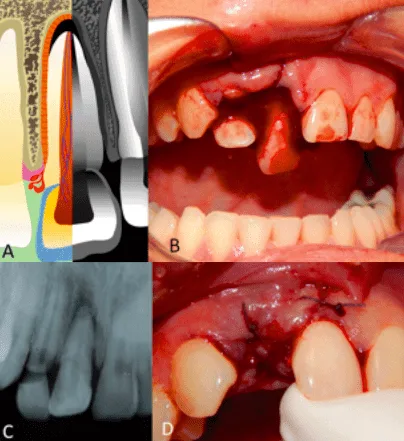

Traumatología dentoalveolar en niños

La cavidad bucal en los primeros años de vida es la zona anatómica que sufre mayor número de traumas debido a la falta del desarrollo motriz en los niños. No obstante los trauma

tismos dentales y dentoalveolares pueden suscitarse en cualquier época de la vida y afectar tanto a la dentición decidua y mixta como a la permanente. El estomatólogo debe estar preparado para ofrecer un tratamiento de urgencia a cualquier paciente traumatizado de cavidad oral, consciente de las repercusiones neurológicas que un traumatismo dentofacial

puede ocasionar en el paciente. El objetivo del presente artículo es describir los traumatismos dentales y dentoalveolares, así como sus alternativas de

tratamiento tanto en la dentición primaria como en la permanente.